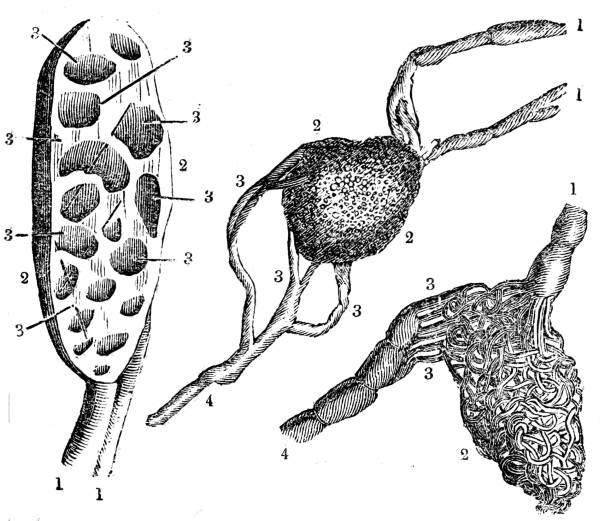

Fig. CXXXVIII.—

View of the Bronchial Tubes terminating

in Air vesicles.

Fig. 138.Fig. 139.

External view.—1. Bronchial tube. 2. Air vesicles. Fig.

139. The same laid open.